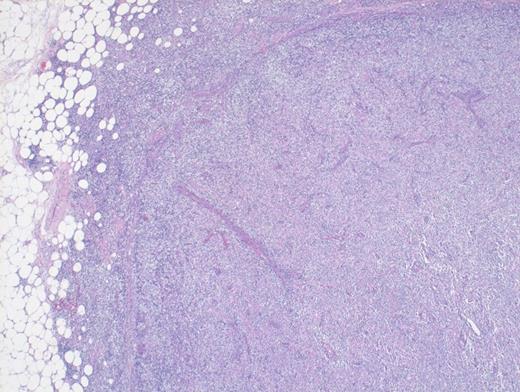

A 73-year-old woman with a history of autoimmune hepatitis presented with abdominal pain and fever. On further examination, the patient was noted to have hypergammaglobulinemia, elevated lactate dehydrogenase (LDH), and diffuse lymphadenopathy on imaging. An excisional biopsy of a superficial lymph node was performed. The images below are of a hematoxylin & eosin stain depicting architectural effacement by this proliferation of medium sized mononuclear cells (Figures A and B) containing numerous wisps of follicular dendritic cell meshworks (Figure C) and few scattered Epstein-Barr virus (EBV)+ cells (Figure D).

Hematoxylin and Eosin Stain Depicting Architectural Effacement by this Proliferation of Medium Sized Mononuclear Cells.

Angioimmunoblastic T-cell lymphoma (AITL) is histologically identified by T-cells having ample clear cytoplasm in a background of prominent vasculature and a mixed inflammatory microenvironment (plasma cells, histiocytes, and immunoblasts). The process effaces the typical nodal architecture with retraction of the peripheral cortical sinuses, in addition to numerous new follicular dendritic meshworks outside of the follicles in the perivenular regions. There are numerous associated reactive B-lineage immunoblasts in the background in addition to the neoplastic T-cells.1 This specific case was positive for CD3 and CD4 on the clear cells.